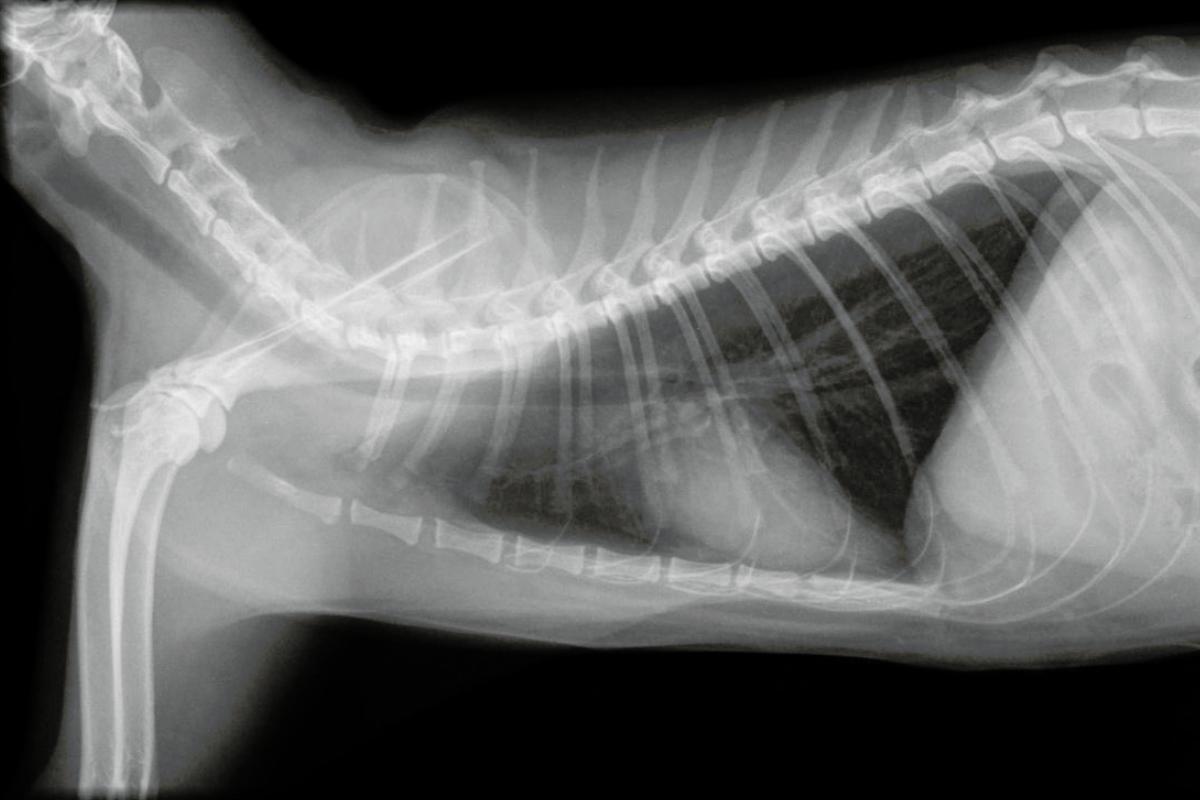

Sintomas como falta de ar, taquipneia e sons pulmonares reduzidos tornam altamente provável um diagnóstico de efusão pleural. Uma radiografia pode revelar a presença de fluido no espaço pleural, pois impede a visualização normal dos pulmões, e o ultrassom pode ser usado na suspeita ou para deduzir que tipo de fluido é (transudado, sangue, linfa, pus), com informações claras sendo obtidas pela análise do fluido após toracocentese por contagem de células, citologia e bioquímica. Em caso de suspeita de infecção, o fluido deve ser colhido.